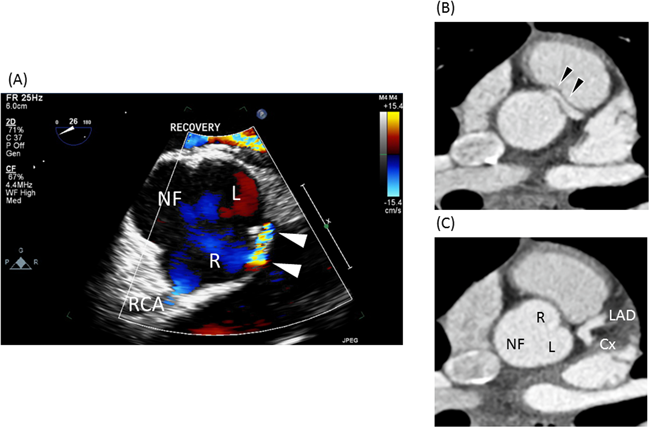

Fig. 4に16歳男児の自験例(AAOLCA-IA)を示す.この症例は学校でのマラソン中に心室細動から心肺停止となり自動体外式除細動器(AED)による蘇生を受けた後に当院へ搬送された.神経学的後遺症なく回復し,冠動脈の大動脈壁内走行部位に対してunroofingを施行した.

Pediatric Cardiology and Cardiac Surgery 32(2): 95-113 (2016)

Fig. 4 Anomalous aortic origin of left coronary artery: intramural and interarterial course

(A): Trans-esophageal echo: Note the flow acceleration at the entrance of the intramural course of the left main coronary artery (white arrow head).(B): Enhanced CT: left coronary artery arises from the right aortic sinus at an acute angle and courses intramurally and interarterially (black arrowhead).(C): Enhanced CT: left main coronary branches into left anterior descending and circumflex artery.Cx: left circumflex artery; LAD: left anterior descending artery; L: left aortic sinus; NF: non-facing sinus; R: right aortic sinus.